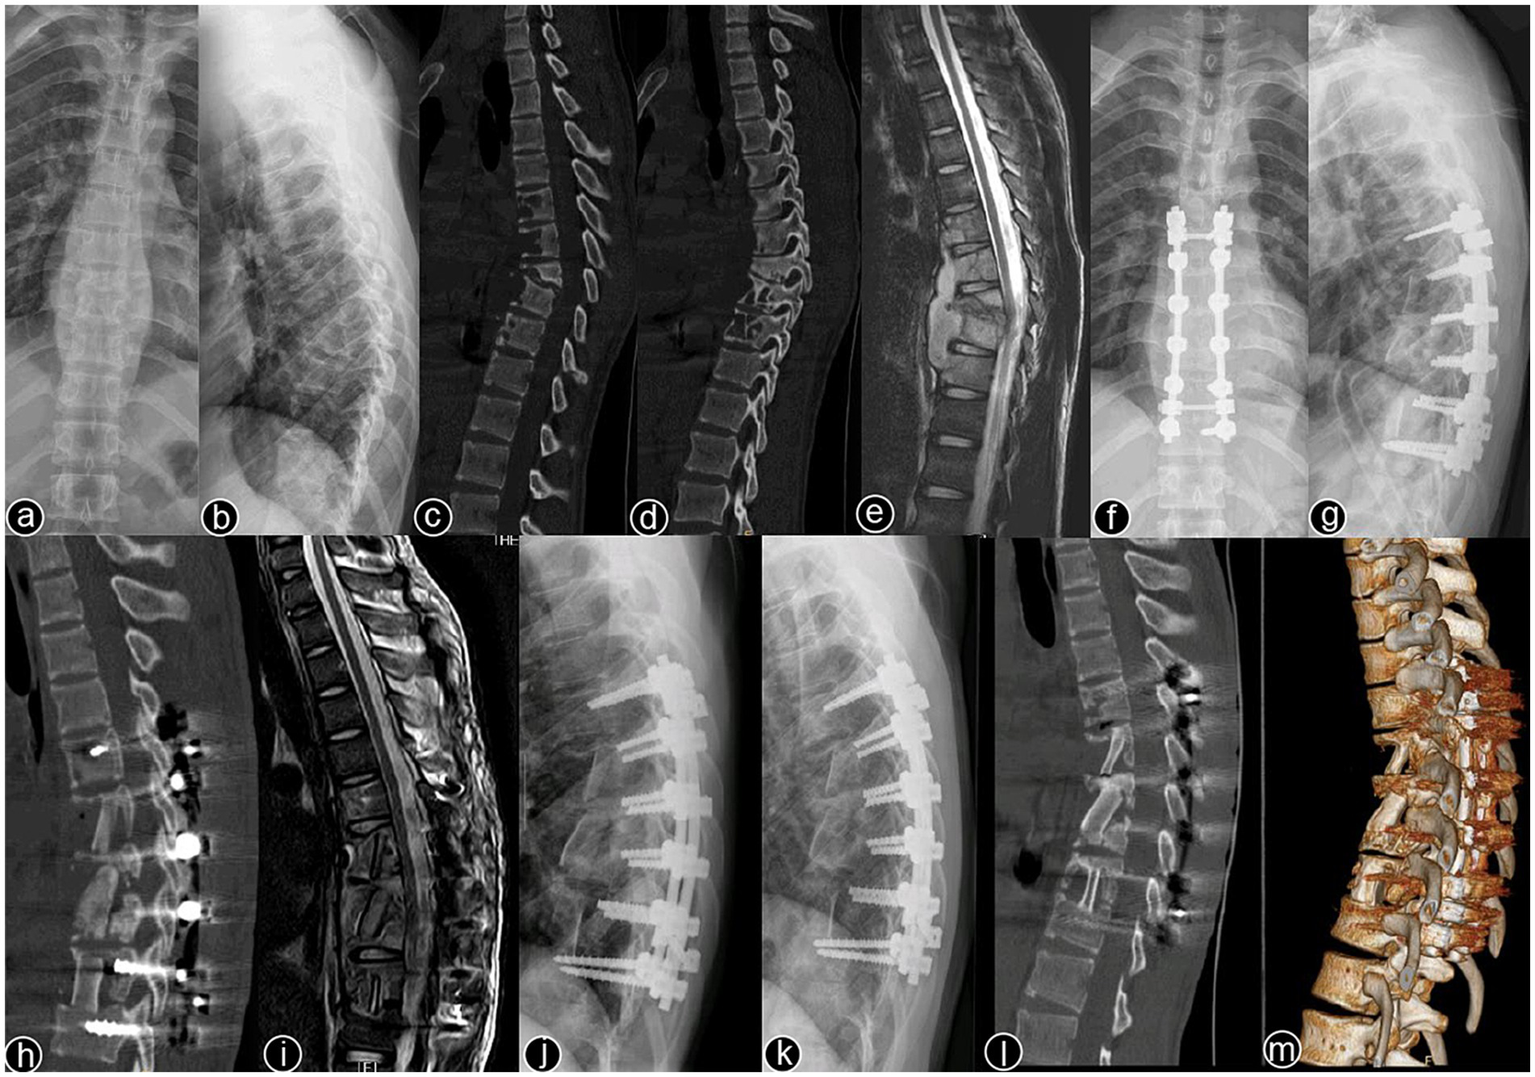

Typical cases are shown in Figures 26, with Figures 24 illustrating intervertebral fixation of the affected vertebrae in three patients from Group A, and Figures 5, 6 demonstrating non-intervertebral fixation in two patients from Group B.

Figure 6

www.frontiersin.org

Figure 6. Patient, female, 45 years old. Diagnosis: spinal tuberculosis (T11–L2). Surgical approach: non-intervertebral surgery. (A,B) Preoperative anteroposterior and lateral X-rays of the thoracic spine show narrowing of the T11–L2 intervertebral space and kyphotic deformity. (C,D) Preoperative thoracic CT shows narrowing of the intervertebral spaces and destruction of multiple vertebral bodies. (E,F) Preoperative thoracic MRI reveals multiple abnormal vertebral signals, narrowing of the intervertebral spaces, and spinal cord compression. (G–I) Immediate postoperative anteroposterior and lateral X-rays, and CT of the thoracic spine show short-screw fixation at T11–L2, proper removal of the intervertebral lesion, and satisfactory bone graft placement. (J–L) Three-year postoperative lateral X-rays, CT, and MRI of the thoracic spine show stable internal fixation without loosening or breakage, good bone graft healing, a clear spinal canal, and no recurrence of the local lesion.